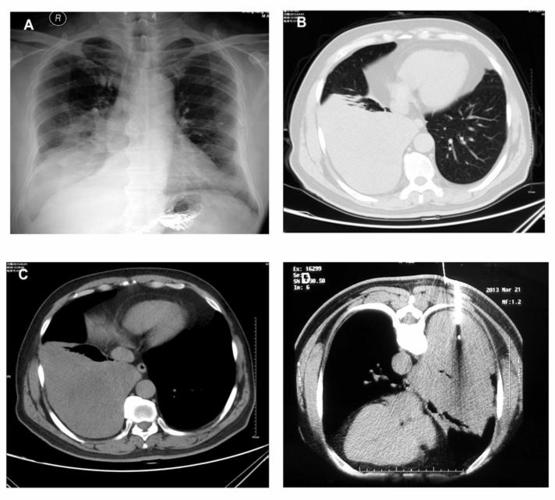

左侧气胸形成伴左下肺局部实变不张,两上肺纤维增殖灶

首页 呼吸内科 典型病例 正文 肺纤维瘤是一种罕见的肺间叶组织良性

左肺下叶见结节状钙化灶是什么意思